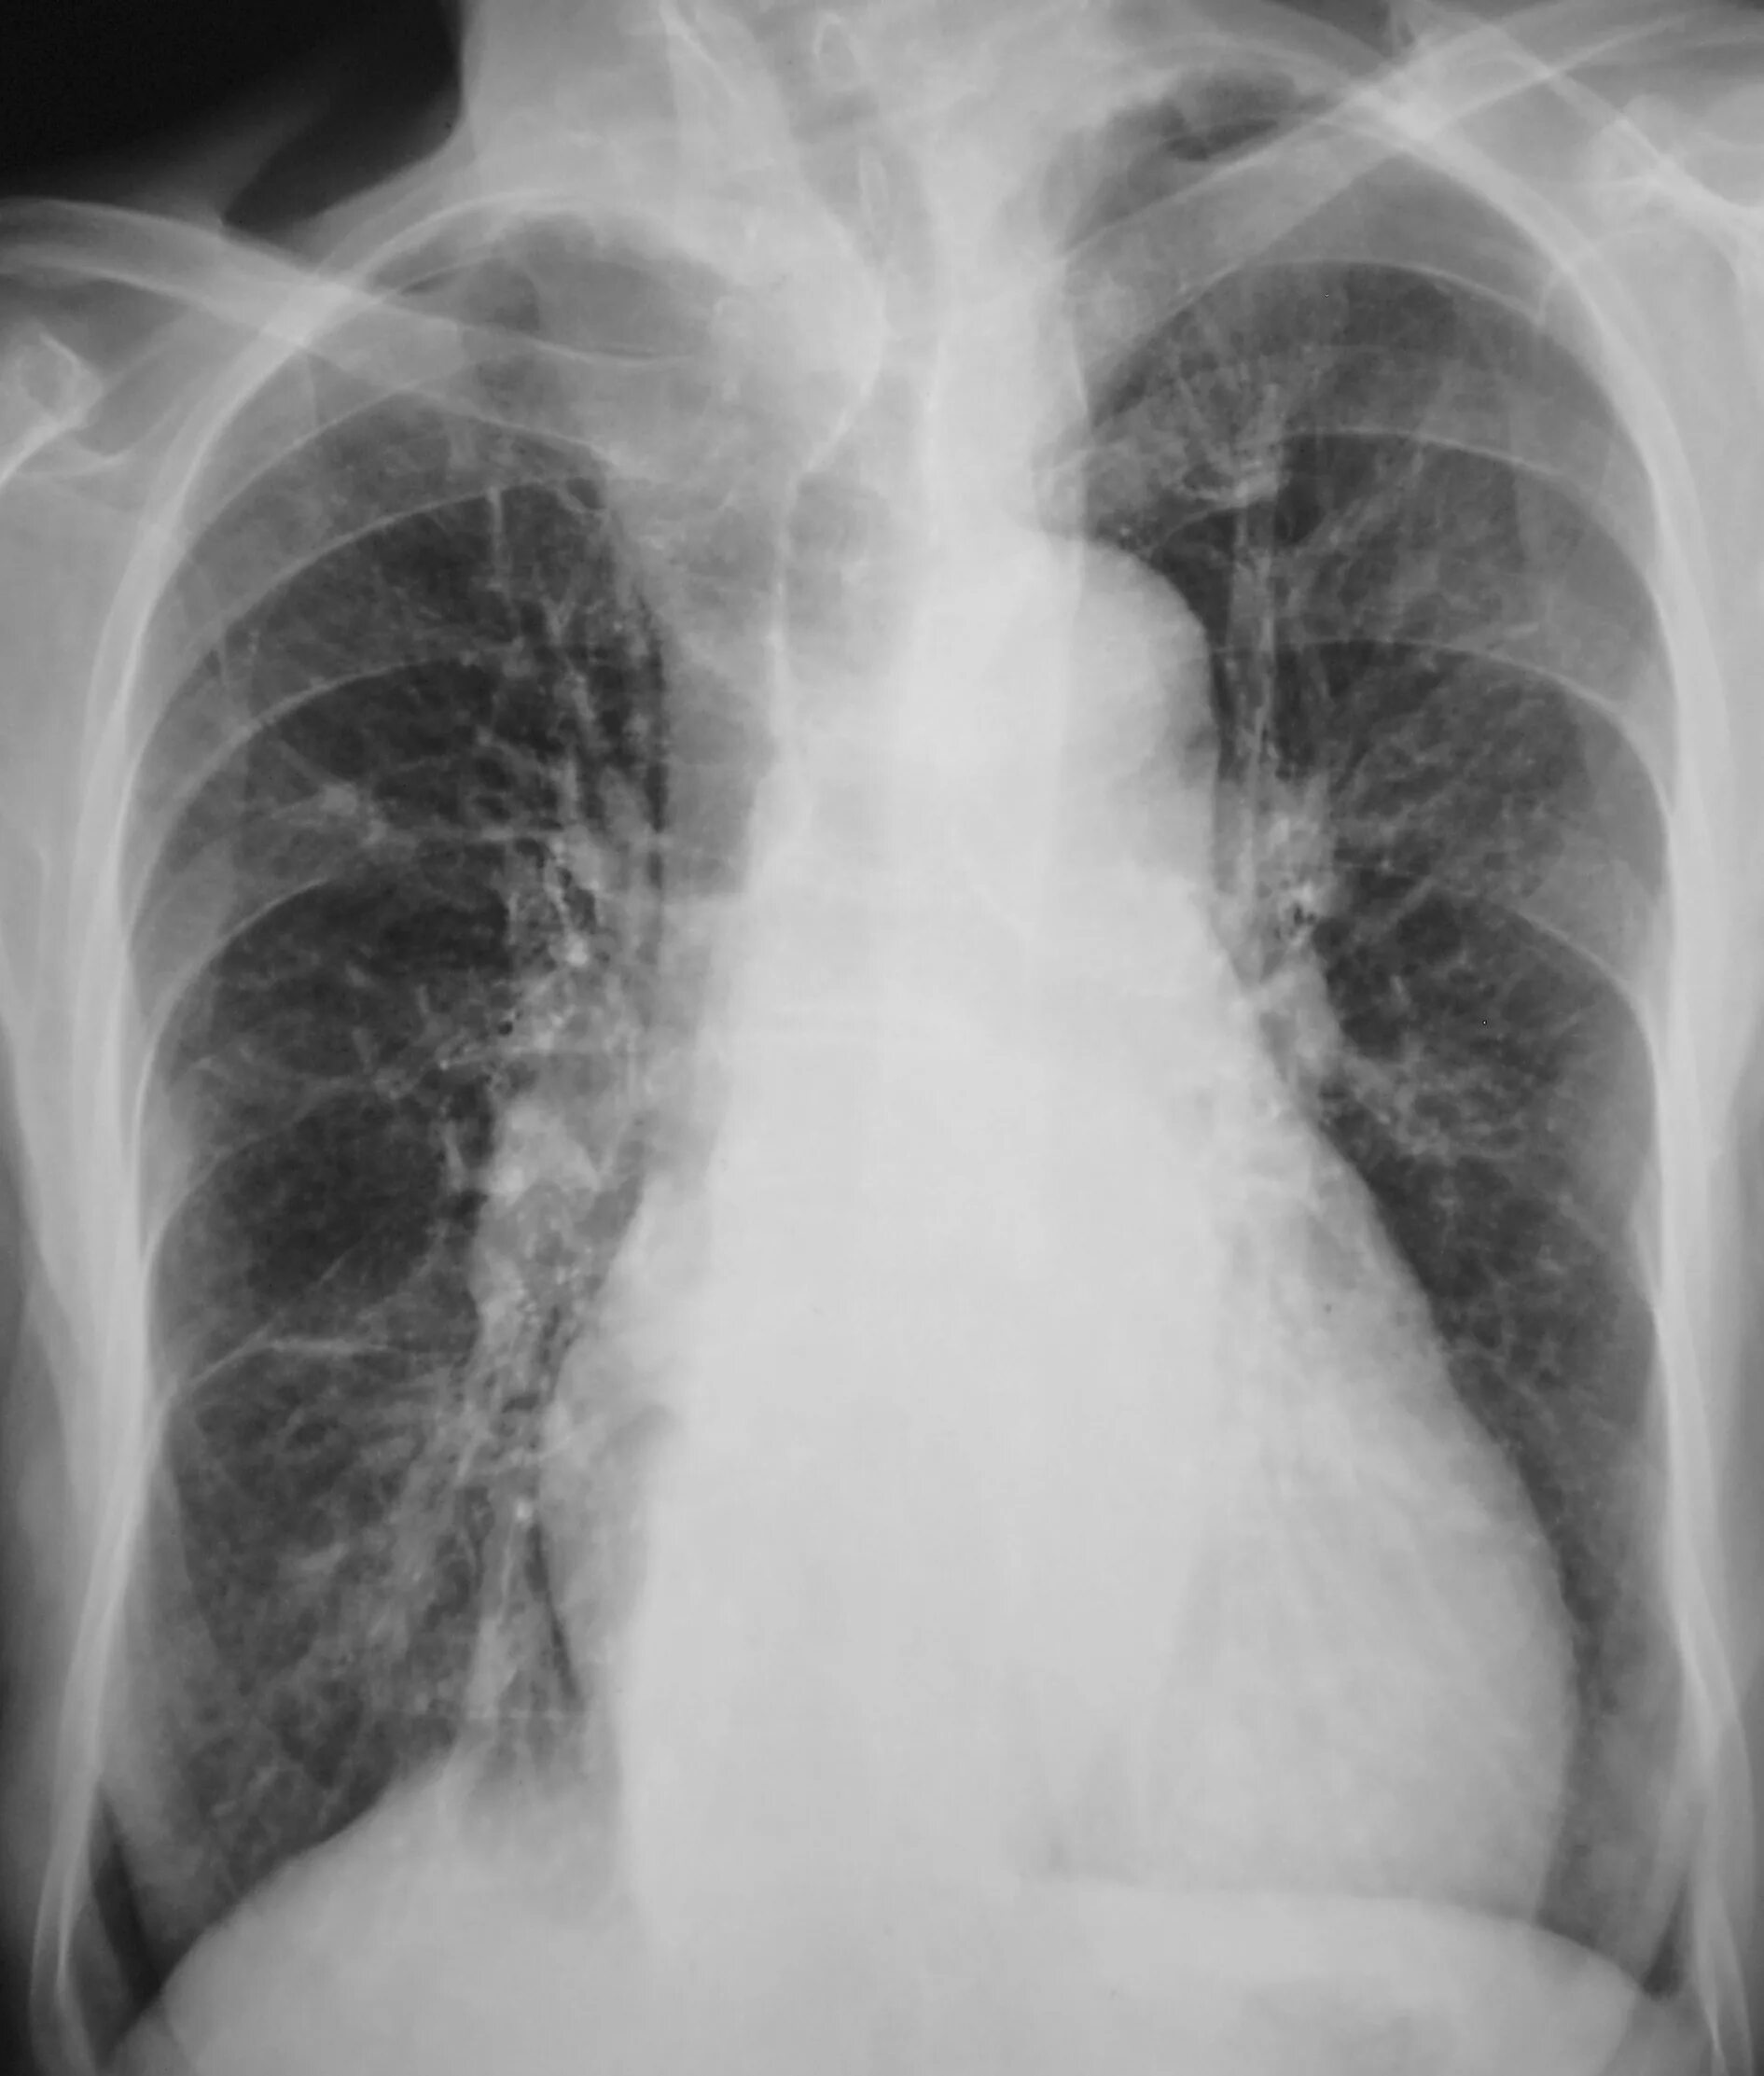

Диффузный эндобронхит